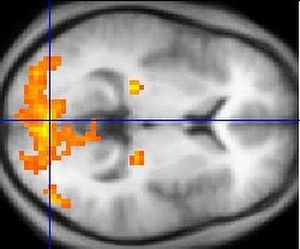

A fMRI scan showing regions of activation in orange, including the primary visual cortex

The visual cortex of the brain is the part of the cerebral cortex responsible for processing visual information.